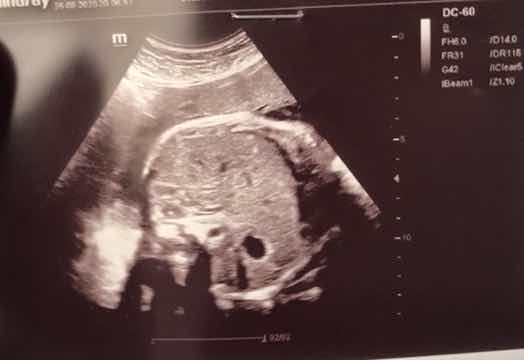

بياض امعاء الجنين هل يعني الطفل داون

مرحبا أنا حامل في الشهر الرابع كنت قد أجريت صورة سونار في الاسبوع ال ١٢ من الحمل و قالت لي...